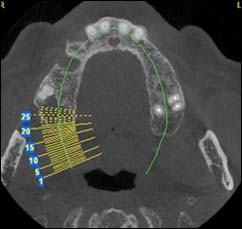

Coupe axiale